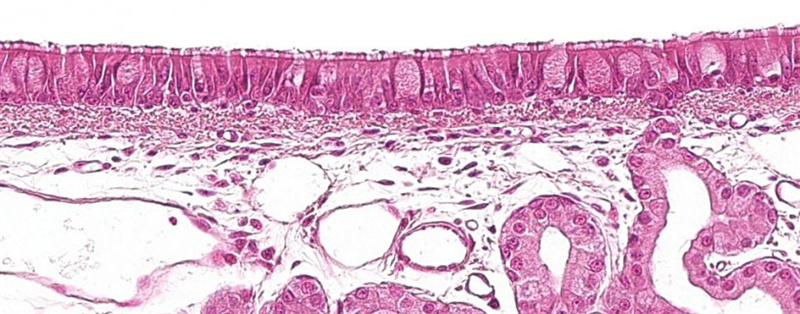

猪呼吸道黏膜

所有粘膜上皮组织(主要是消化道/呼吸道)固有层中都有巨噬细胞和 单核细胞。当粘膜上皮组织破损时,巨噬细胞会大量聚集,与病毒直接接触。